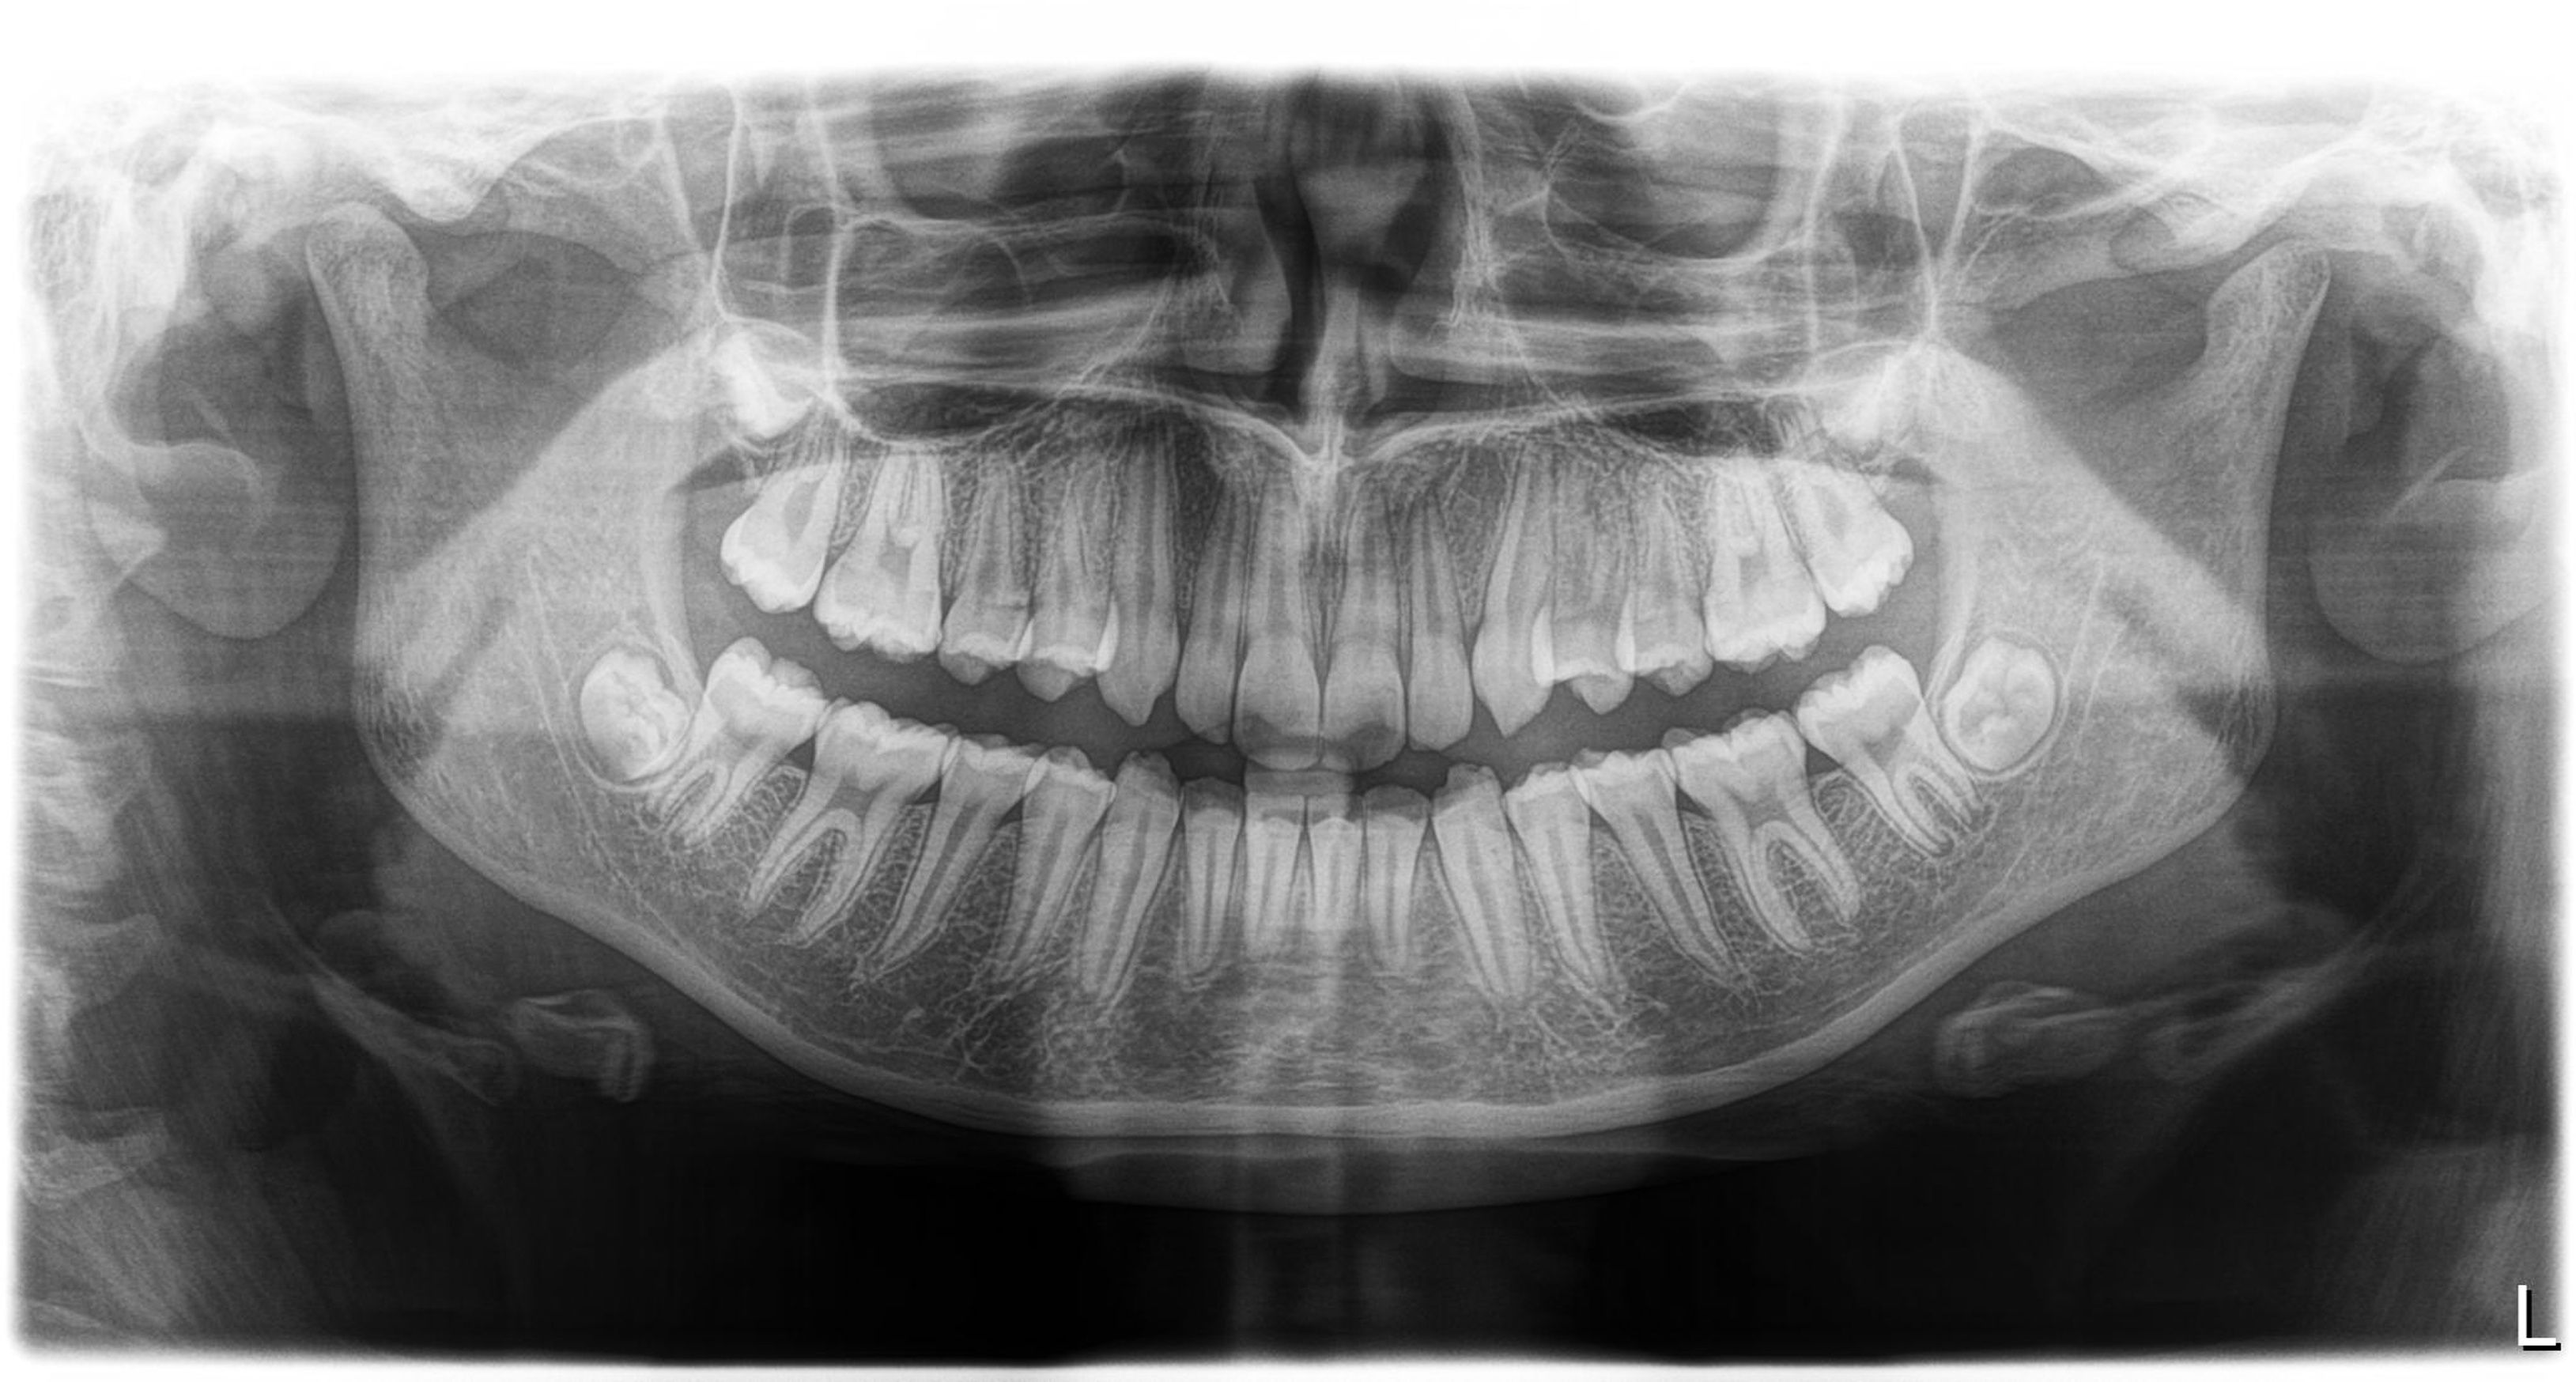

The images were indeed not diagnostic. There was considerable graininess in the images, which is almost always due to underexposure.

As I evaluated the setup in more detail, I saw that every image had a sharpening filter applied, which tends to accentuate the graininess. When I removed the filter, the raw image was completely undiagnostic; it was not capturing enough information.